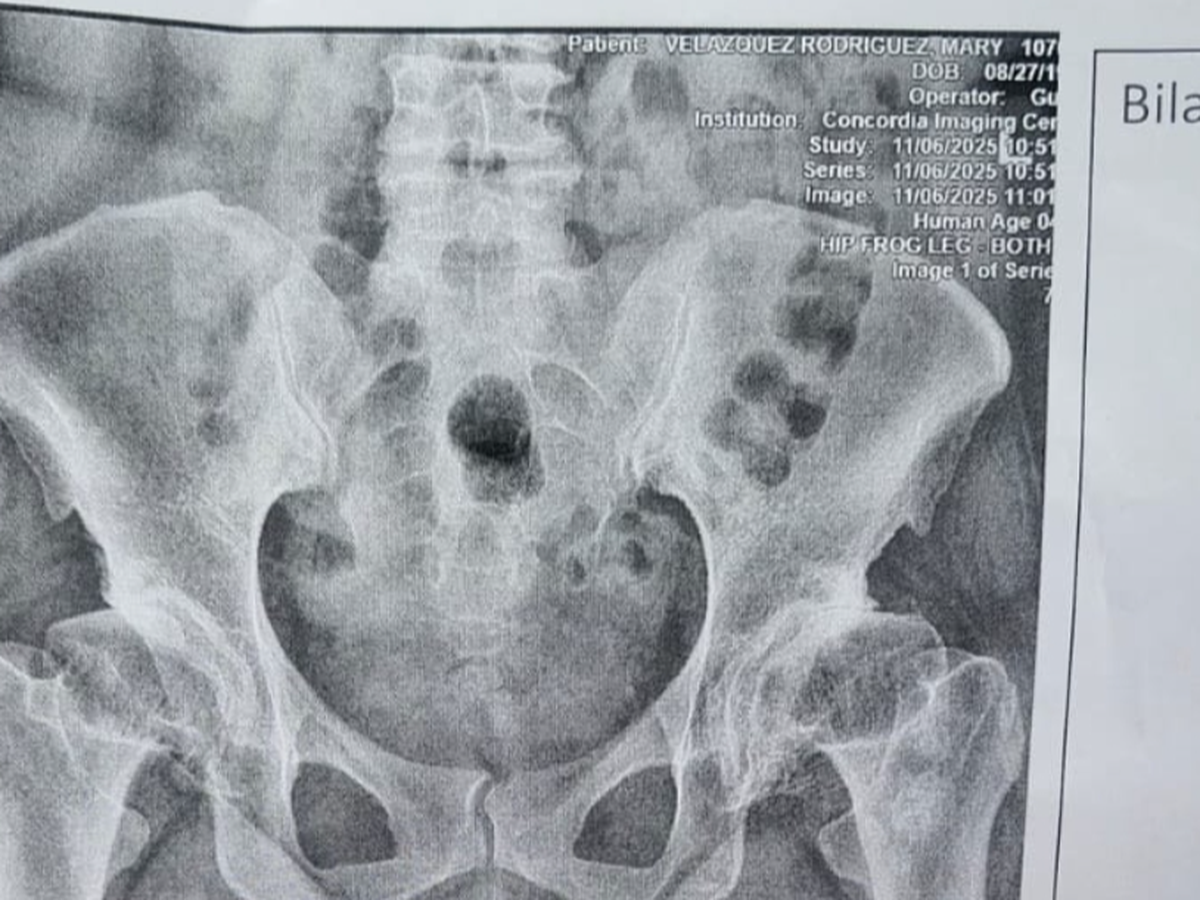

Bendecido, necesito de su ayuda para cubrir gastos médicos ( deducible que el plan médico no cubre); para remplazo de ambas caderas. Es importante para mí ya que no puedo caminar normalmente , soy una persona joven y deseo volver a tener una vida activa y normal.